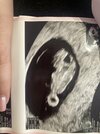

Dziewczyny wróciłam ja pierwszy raz z ręką na sercu siedziałam u lekarza na badaniach 50 min. Zrobił mi trzy badania. 1 badanie ręką, 2 usg dopochwowe i z tego juz wyszło, że dzidzius mierzył 2,11 cm ale mówi ze zrobi mi trzecie badanie przez powłoki brzuszne bo po dwóch cc mam zrosty i wygiętą macice i dlatego słabiej widać obraz zarodka jak zrobił przez powłoki było widać już pięknie dzidziusia i dokładnie mógł zmierzyć 2,21cm

mało tego jego podejście do mnie było tak miłe, że ja pierwszy raz miałam do czynienia z tak cudownym człowiekiem. Jestem w 8 tyg 5 dzień i właczyl mi na 3 sek serduszko. Zapytałam jego o to słuchanie to sie usmiechnil powiedział, że on nie włącza doplera kolorowego bo tylko przy takim jest emitowane ciepło ale to też nie jest takie ciepło, źe dochodzi do porononienia przez to bo gdyby tak było ludzie nie jeździliby dokonywać aborcji do Niemiec tylko tutaj przy usg by dochodziło do poronień. On mi włączył tylko jakieś tam fale aby posłuchać serduszka. Jestem szczęśliwa, spokojna i podjęłam decyzje ze to będzie mu lekarz prowadzący. Założył mi kartę ciąży. Teraz mogę jechać na urlop